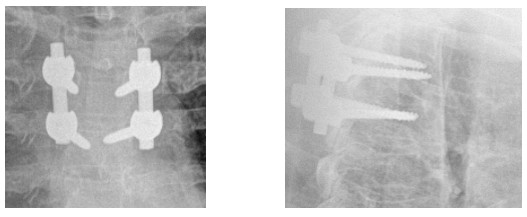

10歲小孩術(shù)前增強(qiáng)MR

術(shù)后復(fù)查不固定位置良好